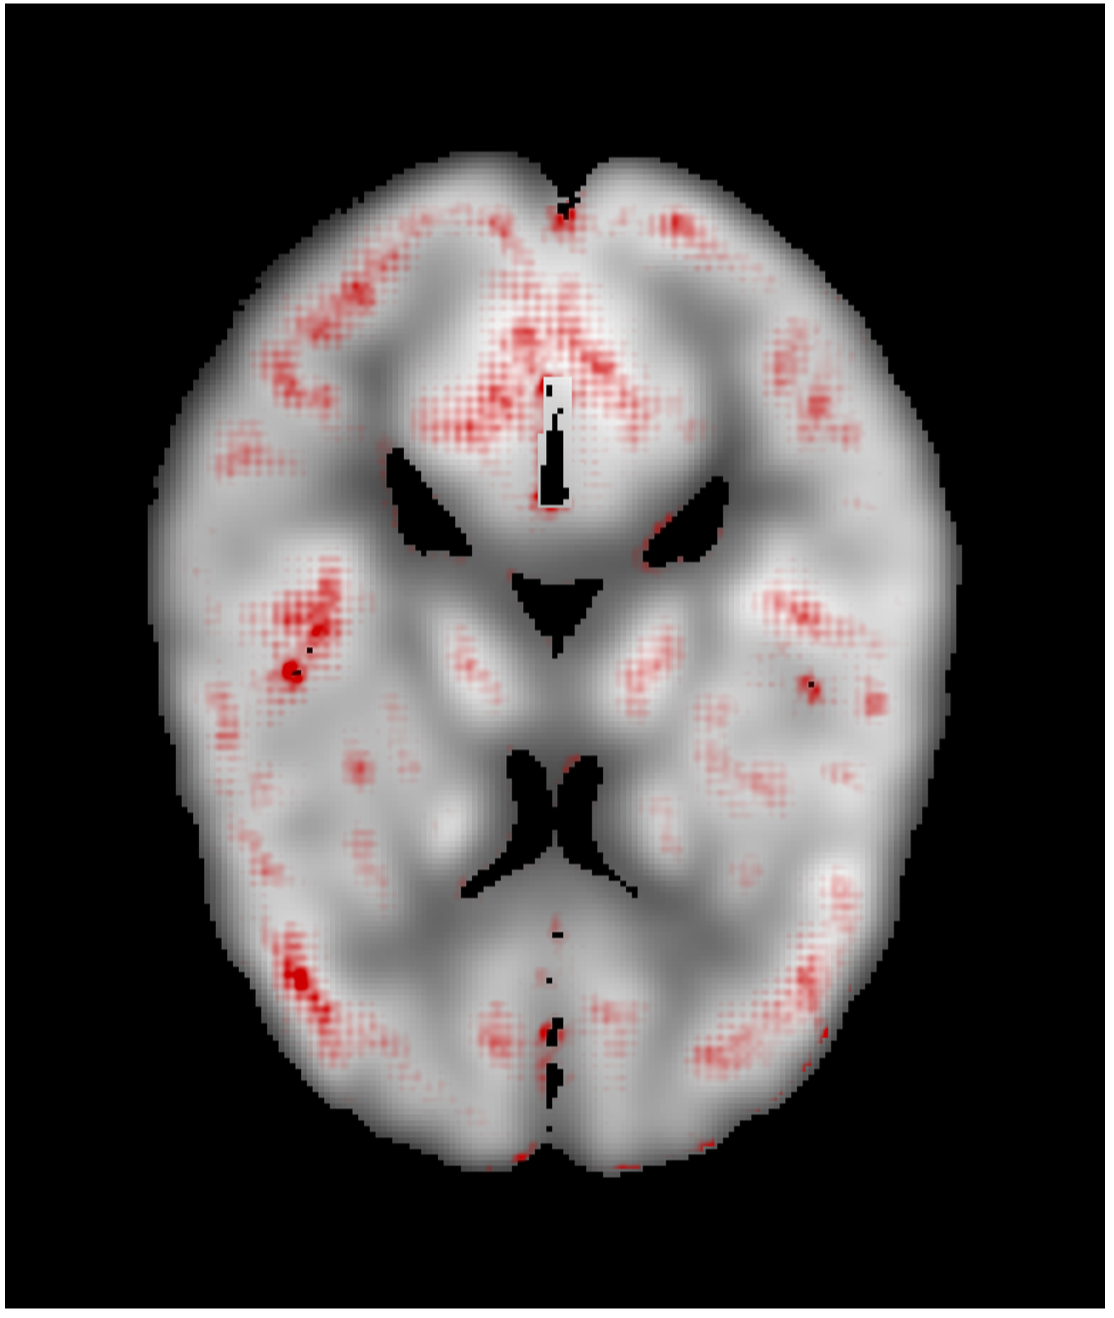

We generated relevance heatmaps for all visualizations methods, averaged over AD PET images in the test dataset. Figure 2 presents the visual comparison of these five methods. The red areas/dots indicate that regions were important for the decision making of the 3D-CNN model. From the result, we can see that all the visualization focuses mostly on similar brain regions. There are some differences, such as the heatmaps generated for the gradient-based methods are distributed. The heatmaps highlight the areas that the CNN network is most susceptible. For the LRP method, the heatmap shows the average relevance of each voxel for contributing to the AD diagnosis score. The heatmaps generated by the occlusion based methods are more focused on the specific regions and cannot administer with large areas of distributed relevance. The reason behind the issue is the occlusion path was not able to cover those areas (for example, the cortex) completely. Brain area occlusion presents very high relevance for the temporal lobe. Since in this method, only one area is covered at a time, that can cause such high importance for one region and minimal relevance for other regions.